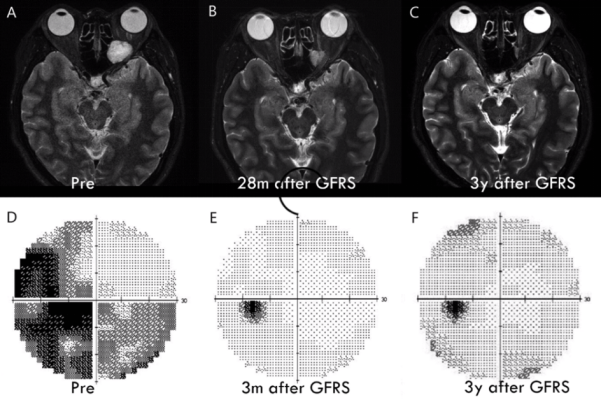

案例分享:一名44岁女性患者,视物不清6年。影像学检查发现4处病灶。多次行γ刀放射性调节,调节效果见下图。2015年研究显示,γ刀放射性调节对海绵状血管瘤效果较好,视力改良为8/8,达68.3%。